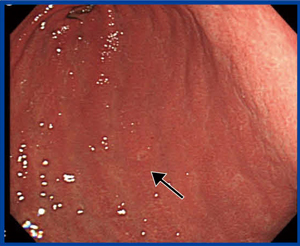

X線検診の追加撮影で,もう1回バリウム造影剤を流すことは,内視鏡検査でインジゴカルミン色素を散布することと同義である。本症例の内視鏡画像でも,インジゴカルミン色素によって前壁の棘状の変化がはっきり見えるようになった(図2)。最近では,NBI(narrow band imaging)や酢酸法なども行われている。

図2 インジゴカルミン色素を散布した内視鏡画像 |